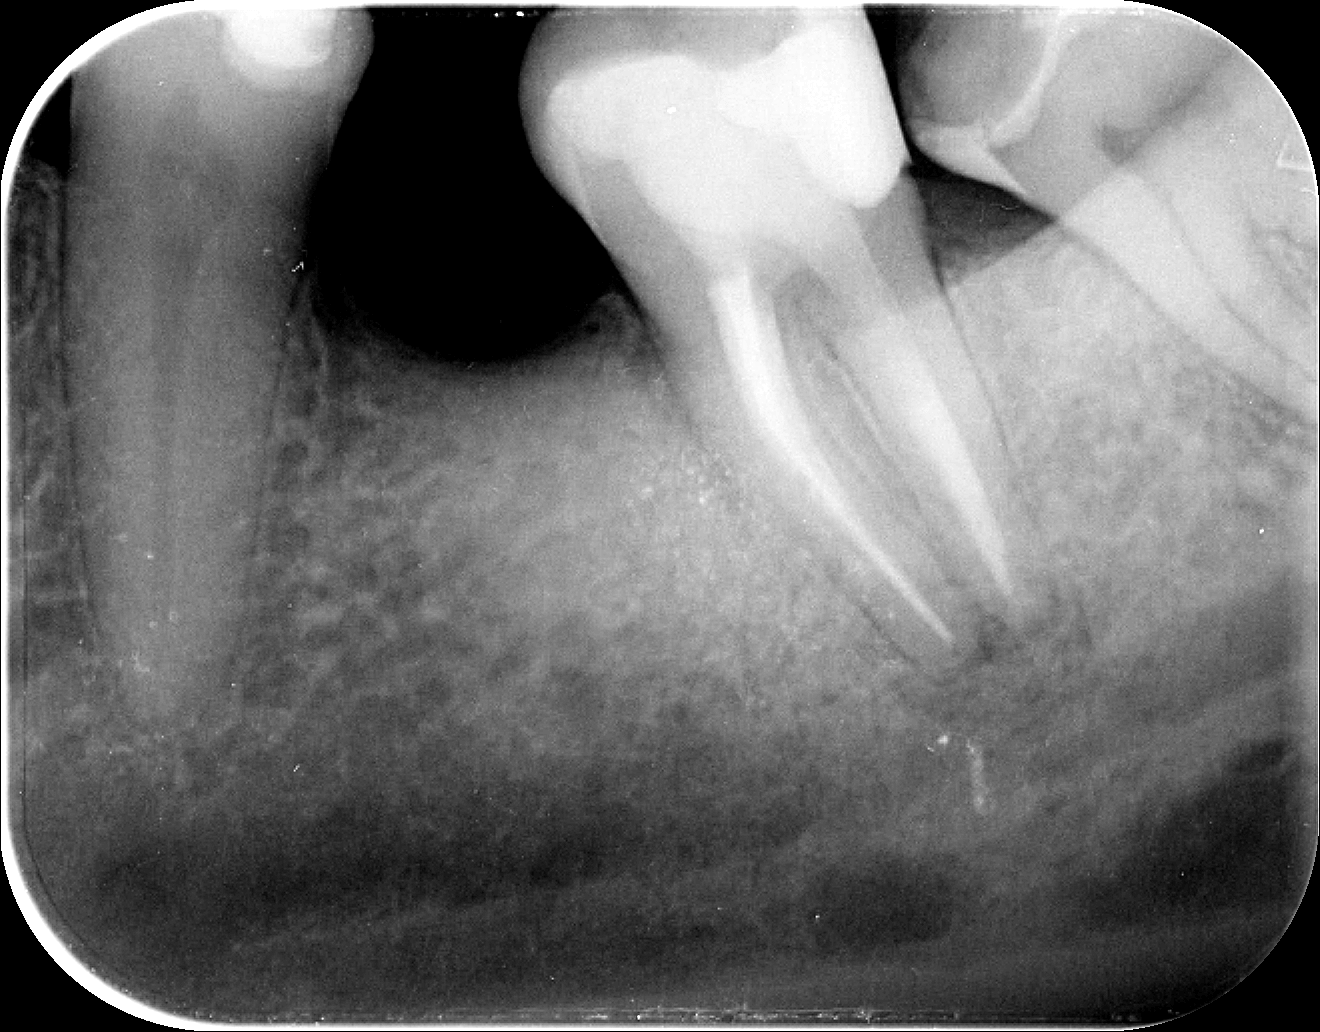

A gyökértömést követően a pácienst fél év múlva rendeltük vissza egy kontrollröntgenre. Saját elmondása szerint a gyökértömést követő pár napban még érzékeny volt a foga, azóta azonban teljesen panaszmentes. Ezt jó hírnek tekintettük, ám szükség volt egy felvételre is, hogy alátámassza a páciens örömteli beszámolóját.

Mint az a kontrollröntgen-felvételen is jól kivehető, a csontban lévő, az eredeti képen látható fekete elváltozás (vagyis a gyulladás) mára jóformán teljesen eltűnt, helyét pedig az egészséges, ép csontszövet vette át. Vagyis végleg bebizonyosodott, hogy a panaszokat okozó gyulladás tényleg megszűnt, a mikroszkópos gyökérkezelésnek köszönhetően a páciens fogát tehát nem fenyegeti az a veszély, hogy el kelljen távolítani.

Remélhetőleg még hosszú évekig, akár élethossziglan tudja még szolgálni tulajdonosát.